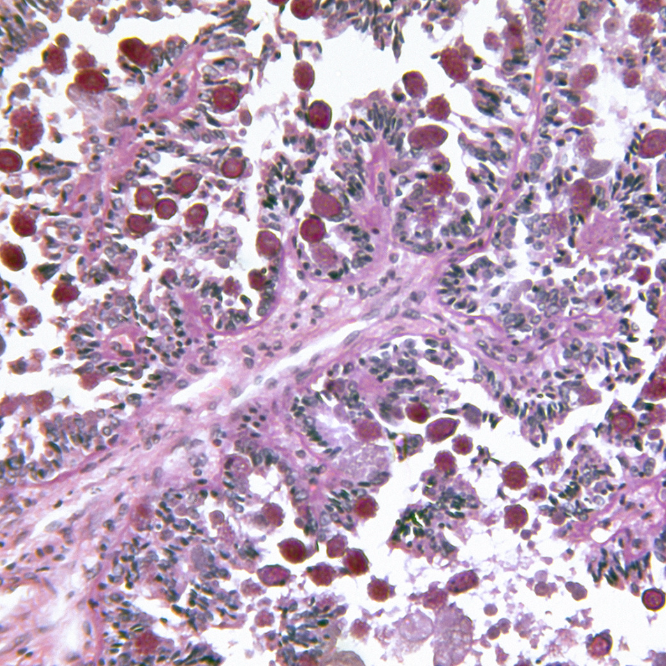

5. Histopathology:

Microscopic examination of intestinal tissue to confirm coccidia presence and evaluate the extent of damage.

3. Post-Mortem Examination:

Inspect intestinal tissue for lesions or damage characteristic of specific Eimeria species.

Look for hemorrhagic or necrotic areas in the gut.